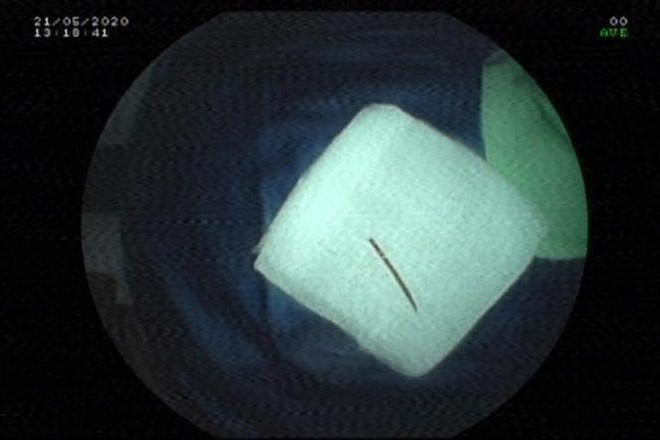

Tai nạn hy hữu do nuốt phải tăm xỉa răng trong khi ngủ ảnh 1Đoạn tăm xỉa răng được nội soi gắp ra từ hậu môn bệnh nhân T. (Ảnh: TTXVN phát)

Sau khi nội soi, bác sỹ Lý Thanh Thư, Khoa Nội tiêu hóa-Gan mật-Nội tiết, Bệnh viện Hoàn Mỹ Đà Nẵng phát hiện có dị vật đâm vào ống hậu môn.

Dị vật là đoạn tăm tre dài khoảng 2cm, tương đương nửa cây tăm bệnh nhân đã ngậm vào tối hôm qua.

Một đầu nhọn của tăm đâm vào ống hậu môn, đầu còn lại trong lòng trực tràng. Bác sĩ đã tiến hành gắp dị vật thành công.